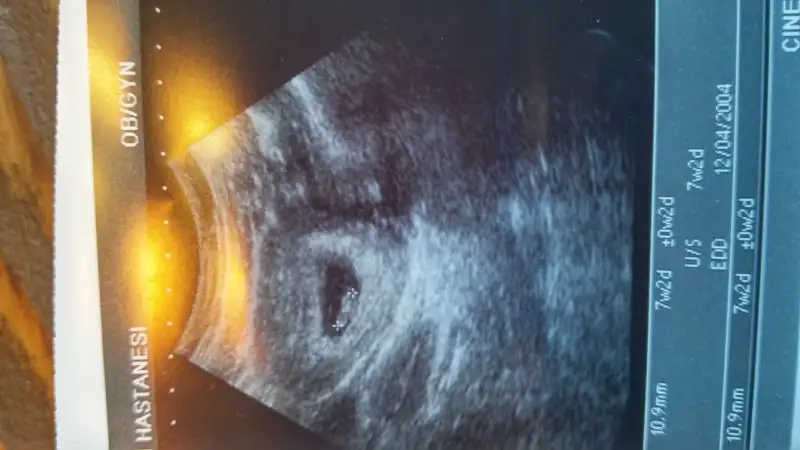

ah be güzelim ultrason o kadar beyaz çıkmış ki zor tahminde bulunuyorum. plasentayı tam seçemedim. seni yanlış yönlendirirm diye korkuyorum. gerçi hepsi tahmin kesin sonuç değil. senin plasenta tamam alt bölümü sarmış.Buda resmimiz

Bu şekilde oldu mu erkek diyorlar canım bebek kesenin solunda olduğunda karından çekilmiş ultrasonsa eğer erkek diyorlar hayırlısı olsun insallahBenim bebisim ne sizce kizlar? Karindan ultrason.